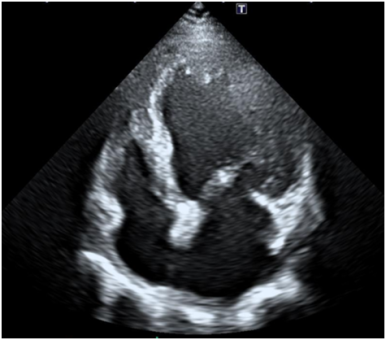

2. 심장초음파

• 심장초음파: 기능 저하 심장초음파: 기능 저하

심장초음파에서 심장기능 저하 상태인 심부전 으로 심장비대가 확인되어, 정밀 검사및 심부전 치료를 위해 상급병원으로 전원.